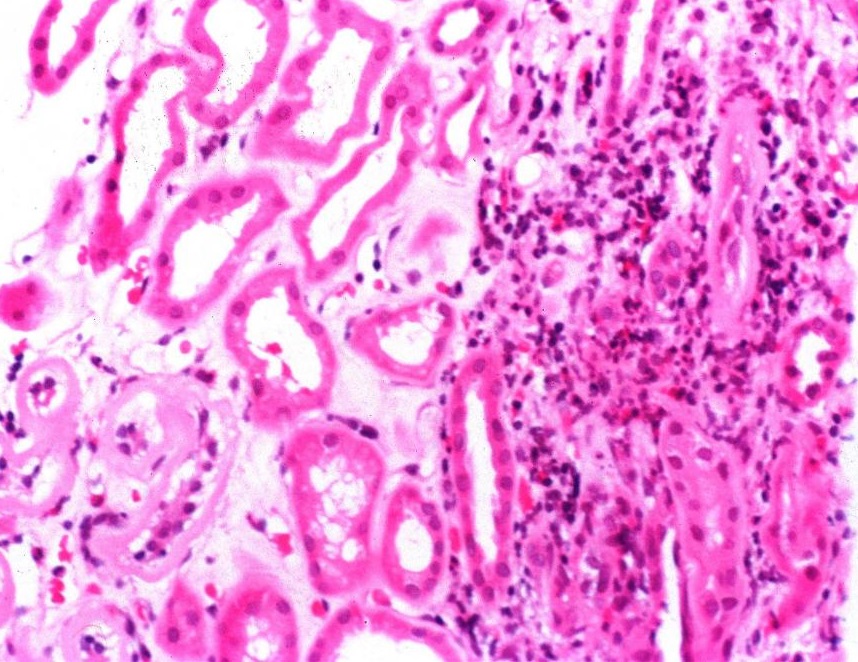

Синдром Гудпасчера – заболевание воспалительного характера, которое поражает мелкие кровеносные сосуды легких и почек.

Врач проводит анализ жалоб пациента, а также анализ анамнеза заболевания. Выполняют общий и биохимический анализ крови, анализ мочи, анализ мокроты, исследование функции внешнего дыхания, рентгенографию легких, реакцию иммунофлюоресценции, анализ на определение в крови специфических белков.